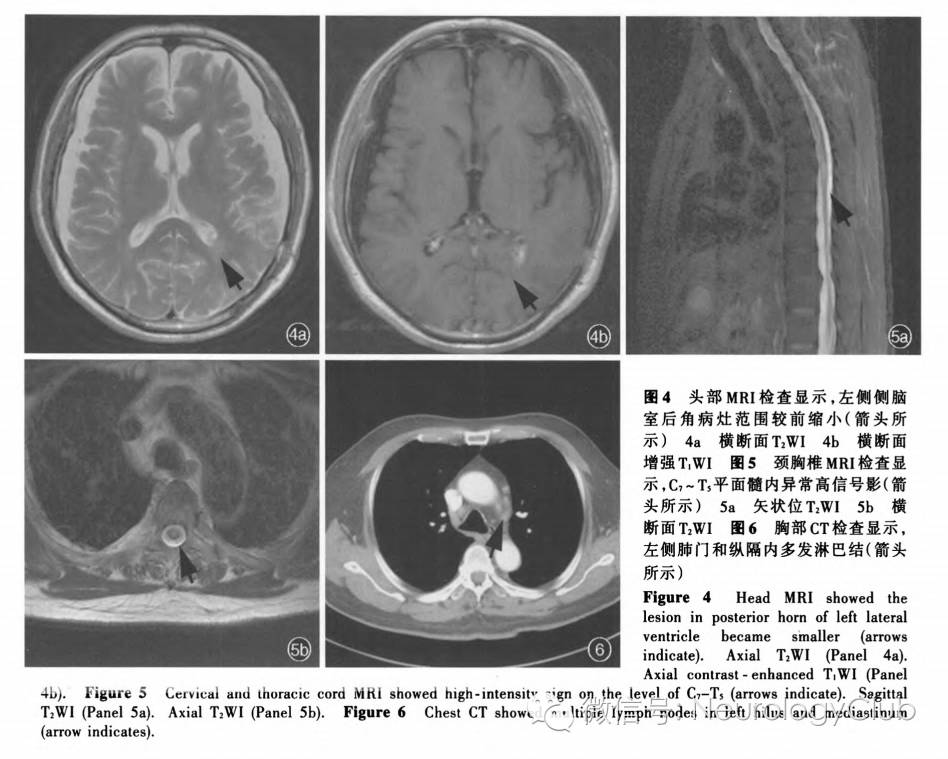

患者男性,69岁,主因行走不稳4个月,双下肢麻木无力、发作性抖动3个月,于2015年11月10日入我院神经科。患者4个月前(2015年7月)无明显诱因出现行走不稳,不自主向左侧歪斜;约1个月后(2015年8月)出现双下肢麻木、无力,行走时前屈、前倾,伴静止时双下肢发作性抖动,动作幅度较大,持续数分钟,2-3次/d,夜间加重、活动或自行按摩后缓解,无头晕、头痛,无意识障碍等。外院头部MRI(2015年9月5日)显示,左侧侧脑室后角和周围占位性病变,伴大面积水肿,增强扫描病变呈结节样强化,考虑脑转移瘤可能性大,不排除分化不良的室管膜瘤等可能;亦可见硬膜下积液,脑白质变性。为求进一步诊断与治疗,于2015年9月14日首次收入我院神经外科,入院后体格检查:右侧颞部视野缺损,左侧额部和耳上皮肤针刺觉减退,左下肢肌力4级、余肢体肌力正常,肌张力均增高,双侧Babinski征阳性。复查头部MRI显示,左侧侧脑室脉络丛、枕角室管膜下占位性病变(图1),不支持高级别神经上皮组织肿瘤;进一步行18F-脱氧葡萄糖18F-FDG)PET显示,左侧侧脑室后角代谢增高。遂于2015年9月23日行立体定向脑深部病变(左侧侧脑室后角)穿刺活检术。患者住院13d,出院等待病理学检查结果,遵医嘱服用丙戊酸钠缓释片(德巴金)0.50g/次(2次/d)、维生素B1 10mg/次(3次/d)以及甲钴胺(弥可保)0.50mg/次(3次/d)。出院后5d(2015年10月1日)突然出现反应迟钝、睡眠增多、言语不能、持筷不能,双下肢无力、行走不稳加重,遂至我院神经外科急诊就诊。头部CT显示,左侧颞枕叶片状低密度影,提示水肿可能(图2),予甲泼尼龙(美卓乐)20mg/d 口服,治疗3d后每3天减量4mg直至停药,共治疗15d,以及甘油果糖氯化钠注射液250ml/次(2次/d)静脉滴注1d后改为甘油合剂50ml/次(2次/d)口服5d。治疗3d后(2015年10月4日)逐渐好转,言语和思维有逻辑,可识家人,继续上述治疗。至2015年10月10日,脑组织活检病理学检查显示,左侧侧脑室后角少许脑组织,并可见类上皮样肉芽肿结节(图3),建议排除结核病等感染性疾病。遂于2015年10月20日至我院感染科门诊就诊,实验室检查血清结核分枝杆菌感染T细胞斑点试验(T-SPOT.TB)和结核分枝杆菌抗体均呈阴性,红细胞沉降率(ESR)和C-反应蛋白(CRP)均于正常值范围,考虑结核病可能性不大。为求进一步诊断与治疗,于2015年11月9日至我院神经科门诊就诊,体格检查:脑神经未见明显异常,双下肢腱反射活跃,双侧Babinski征阳性,步态正常,可直线行走。复查头部MRI显示病灶较前明显缩小(图4)。予氯硝安定1mg/晚口服,双下肢不自主抖动明显缓解,自觉至10月10日行走不稳已较前好转。门诊以“颅内占位性病变,性质待查”收入院。患者自发病以来,否认口干、眼干、皮疹、光过敏、雷诺现象等,精神、睡眠和饮食正常,小便频繁、大便多年依赖通便药物,体重无明显变化。

辅助检查  实验室检查:血尿便常规、肝肾功能试验、凝血功能均于正常值范围;血清糖化血红蛋白(HbA1c)、叶酸和维生素B12均于正常水平;甲状腺功能试验游离T3(FT3)、游离T4(FT4)均于正常值范围,促甲状腺激素(TSH)4.36 mIU/L(0.27-4.20mIU/L);血管紧张素转换酶(ACE)阴性,抗溶血性链球菌素O(ASO)、类风湿因子(RF)、免疫球蛋白和补体均于正常值范围,抗核抗体(ANA)谱阴性;肿瘤标志物筛查未见异常;血清抗N-甲基-D-天冬氨酸(NMDA)抗体,抗电压门控性钾离子通道(VGKC)抗体,抗Hu、Yo、Ri抗体,视神经脊髓炎(NMO)特异性抗体NMO-IgG均于正常水平。腰椎穿刺脑脊液压力150mmH2O(1mmH2O=9.81×10^-3kPa,80-180mmH2O),白细胞计数4×10^6/L(<5×10^6/L),蛋白定量670mg/L(150-450mg/L)、葡萄糖和氯化物均于正常值范围,细菌、真菌、淋球菌、奴卡菌涂片阴性,抗酸染色和墨汁染色阴性,EB病毒(EBV)DNA、巨细胞病毒(CMV)DNA、TORCH10项[包括弓形虫(TOX)、风疹病毒(RV)、巨细胞病毒、I型和II型单纯疱疹病毒(HSV-1和HSV-2)]均阴性,特异性寡克隆区带可疑阳性,髓鞘碱性蛋白(MBP)于正常值范围。影像学检查:胸椎MRI增强扫描,C7-T5平面髓内异常强化征象(图5);胸部CT和高分辨力CT增强扫描显示,双肺下叶胸膜下少许条索状影;左侧肺门和纵隔内多发性稍大淋巴结(图6);双侧胸膜增厚,未见明显强化。甲状腺超声显示,甲状腺体回声欠均匀,颈部未见明显肿大淋巴结。腹部超声未见明显异常。泌尿系统超声显示,膀胱多发结石,前列腺增大。

诊断与治疗经过  经神经科会诊脑组织活检病理学结果,光学显微镜下可见非干酪样类上皮样肉芽肿结节,最终诊断为神经系统结节病。予甲泼尼龙1000mg/d静脉滴注冲击治疗,治疗5d后改为60mg/d口服,每周减量5mg。患者共住院27d,出院时双下肢麻木无力症状缓解,行走不稳好转;双上肢肌力5级、右下肢5-级、左下肢4+级,双足背屈、趾屈5级。出院后1个月(2016年1月4日)至门诊随访,行走不稳好转30%,下肢肌阵挛样抖动发作频率明显减少,体格检查:脑神经未见明显异常,四肢肌力5级、肌张力正常,双侧膝腱反射活跃,双侧Babinski征阳性,步基宽,Romberg征阳性。遂将泼尼松剂量调整为35mg/d口服,嘱患者随访调整药物剂量;1个月后(2016年2月)随访,运动功能无变化,未继续好转,再次将泼尼松增量至40mg/d口服,复查头部和颈胸椎MRI显示,原病灶明显陈旧;2个月后(2016年4月)随访,病情再次好转,可独立从椅子上站起、行走,体格检查:四肢肌力5级,其余无变化,遂将泼尼松剂量减至40mg/d隔日口服;3个月后(2016年7月)随访,出现下肢无力症状加重趋势,近2周无法独立行走,需搀扶,坐位起立困难,下肢仍不自主抖动,体格检查:双上肢肌力5级、髂腰肌肌力2+-3-级、股四头肌肌力4级、双足背屈4级(左侧弱于右侧),肌张力均正常,双侧腹股沟以下针刺觉减退,复查血清血管紧张素转换酶阴性,头部和颈胸椎MRI未见明显变化,再次将泼尼松增量至40mg/d口服;1个月后(2016年8月)随访,双下肢肌力再次较前好转,继续予泼尼松40mg/d口服,目前仍在随访中。